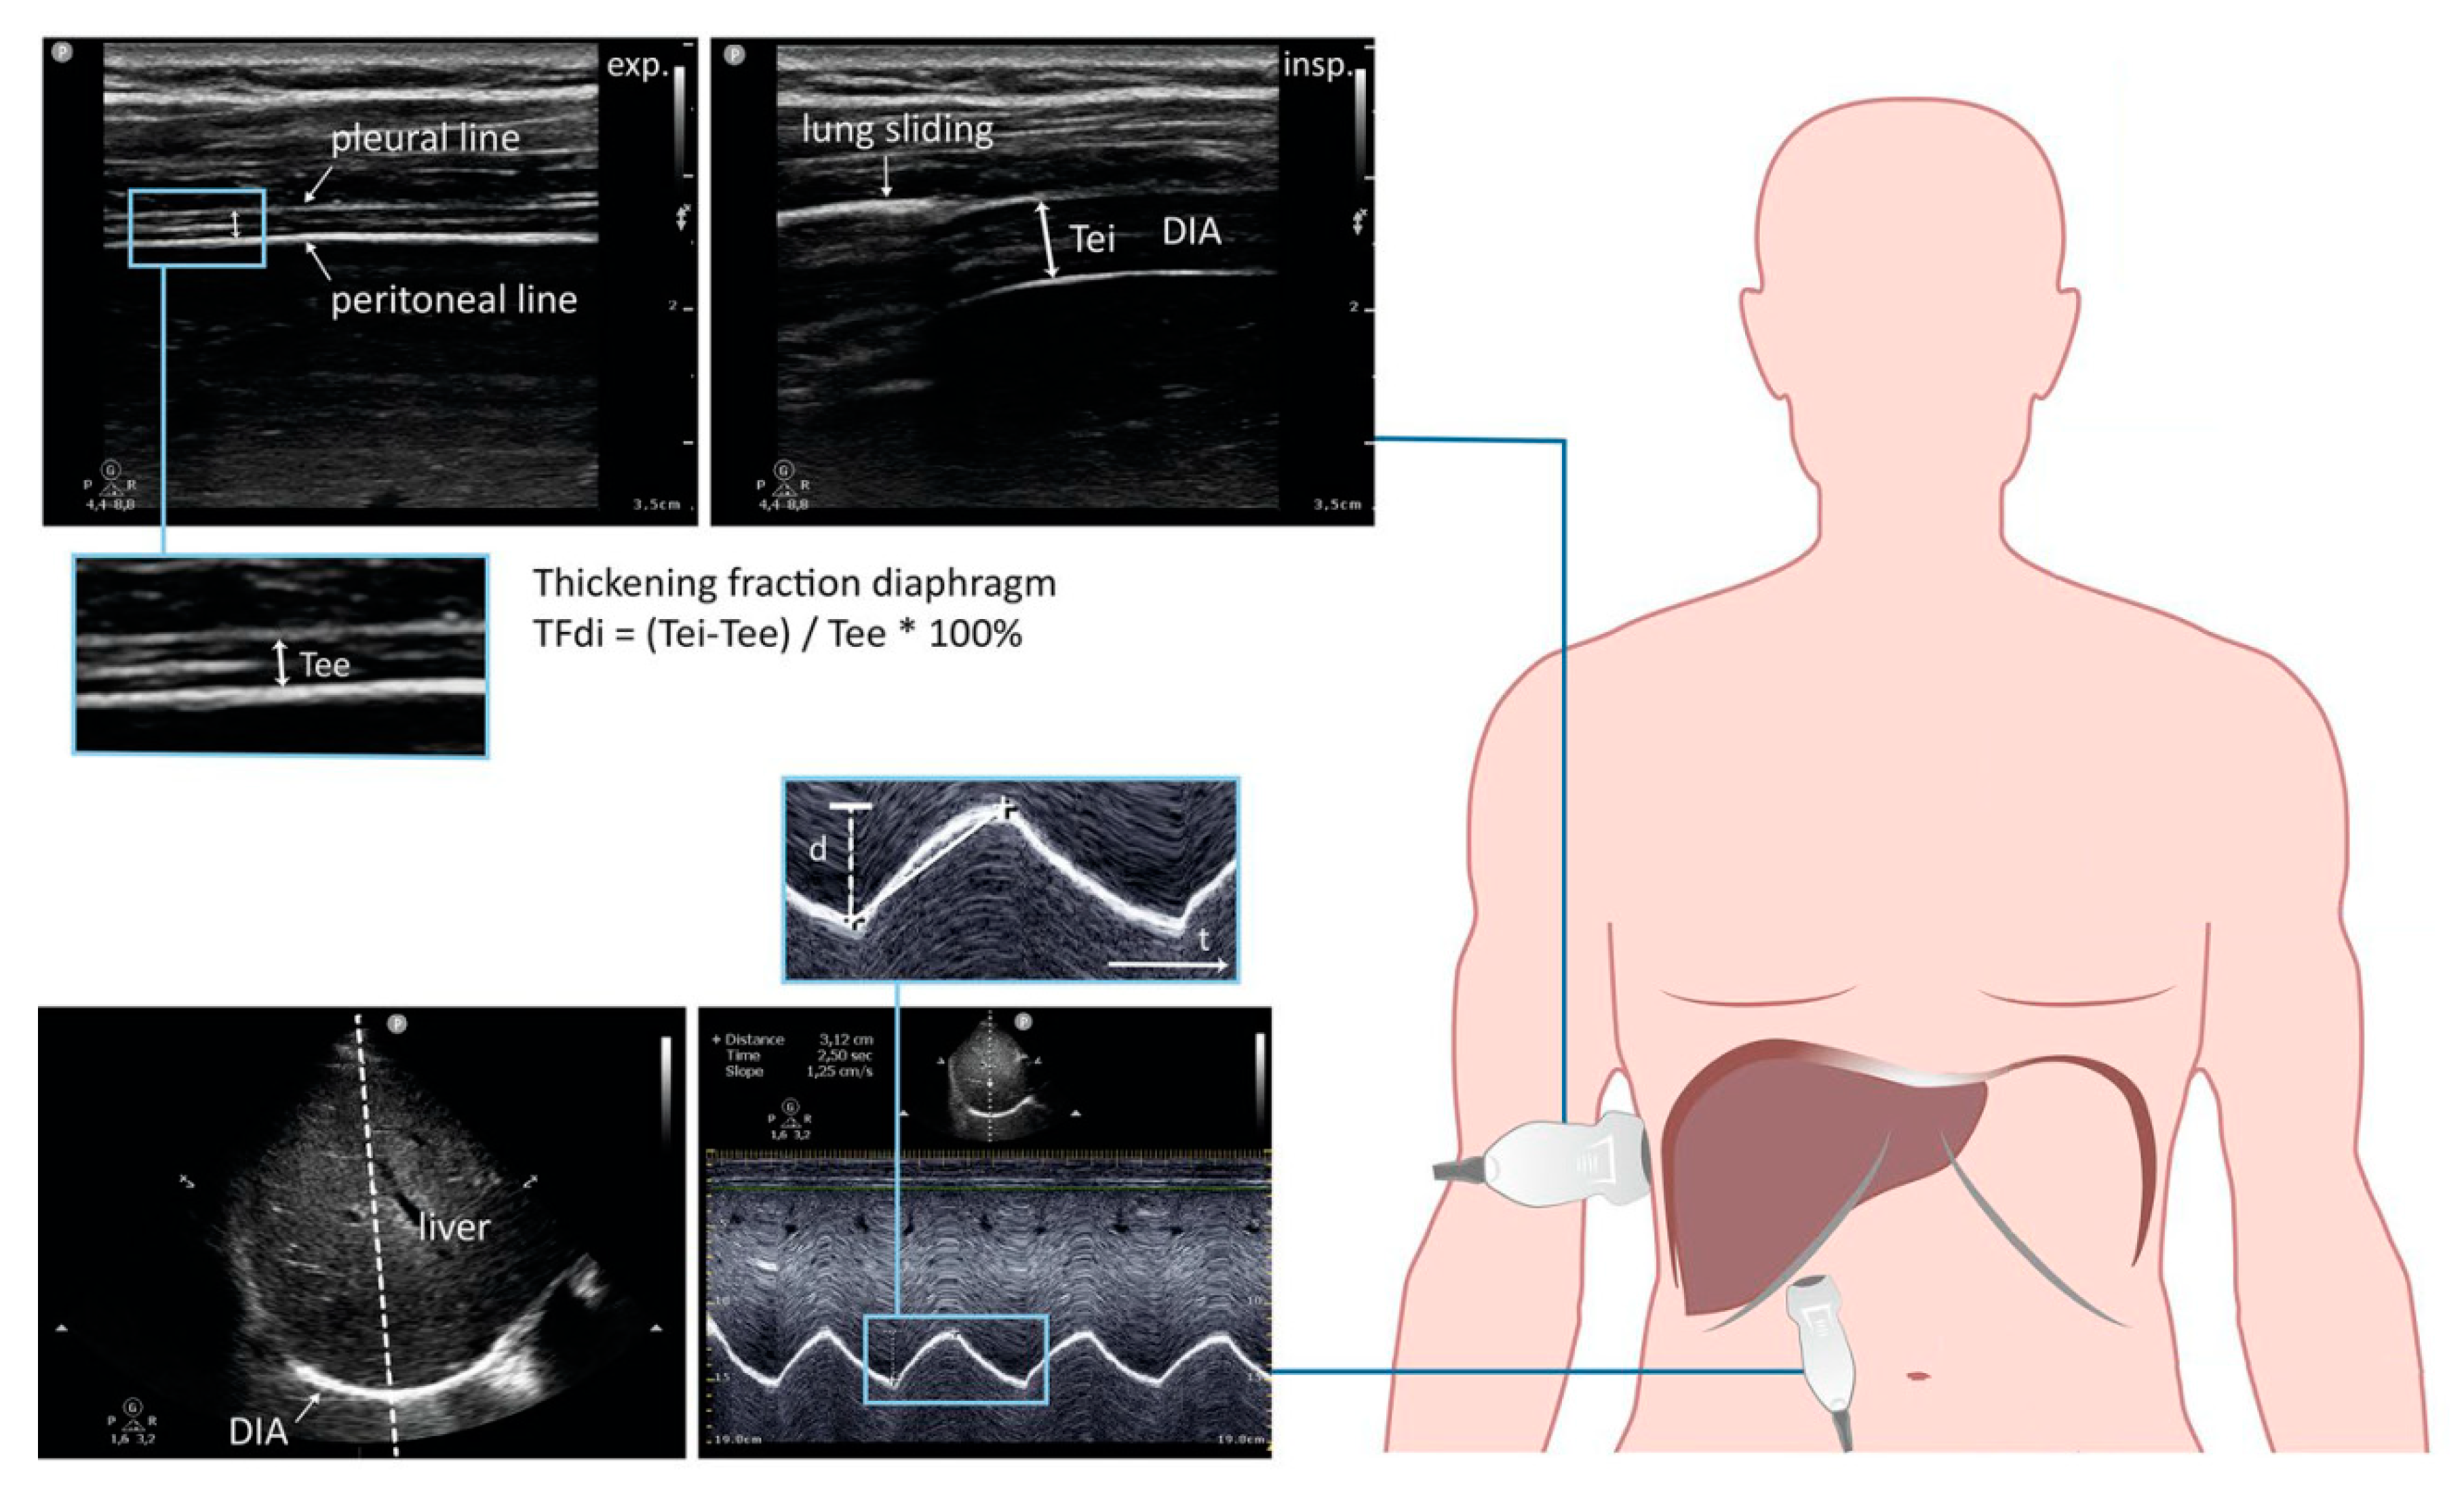

Diaphragm Movement And Contractility Evaluation By Thoracic Ultrasound Diaphragmatic Excursion Is Used For What Palpation of the chest includes evaluation of thoracic expansion, percussion, and evaluation of diaphragmatic excursion. Diaphragmatic excursion values presented in this study can be used as reference values to detect diaphragmatic dysfunction in. This study looked at the role of diaphragm excursion (de) and thickening fraction in predicting successful extubation from. Although the pathophysiological mechanisms involved in the development of. Diaphragmatic Excursion Is Used For What.